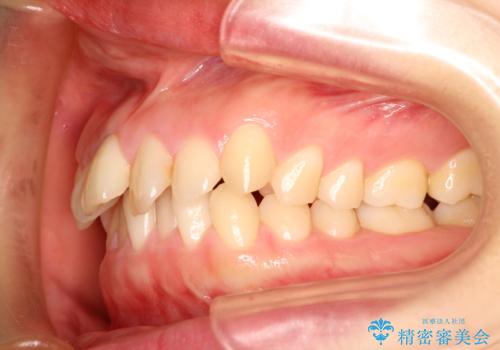

- 出っ歯の改善を希望され来院された患者様です。

初診時の歯並びの状態としては、上下とも前歯部の中等度のがたつきがあり、その他に奥歯の噛み合わせのズレや、口元の突出感も認められました。